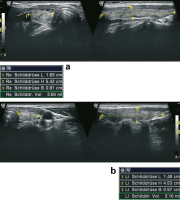

Abbildung 1a-b: 56-jährige Patientin mit subakuter Thyreoiditis im linken Lappen. 1a: Der rechte Schilddrüsenlappen zeigt lediglich einzelne degenerative Veränderungen und kleine echoarme Umbauzonen (links Querschnitt, rechts Längsschnitt). 1b: Der linke Lappen ist mit 15 ml deutlich vergrößert und zeigt inmitten des normalen Schilddrüsenparenchyms zahlreiche echoarme, landkartenartig konfigurierte echoarme Areale (links Querschnitt, rechts Längsschnitt).